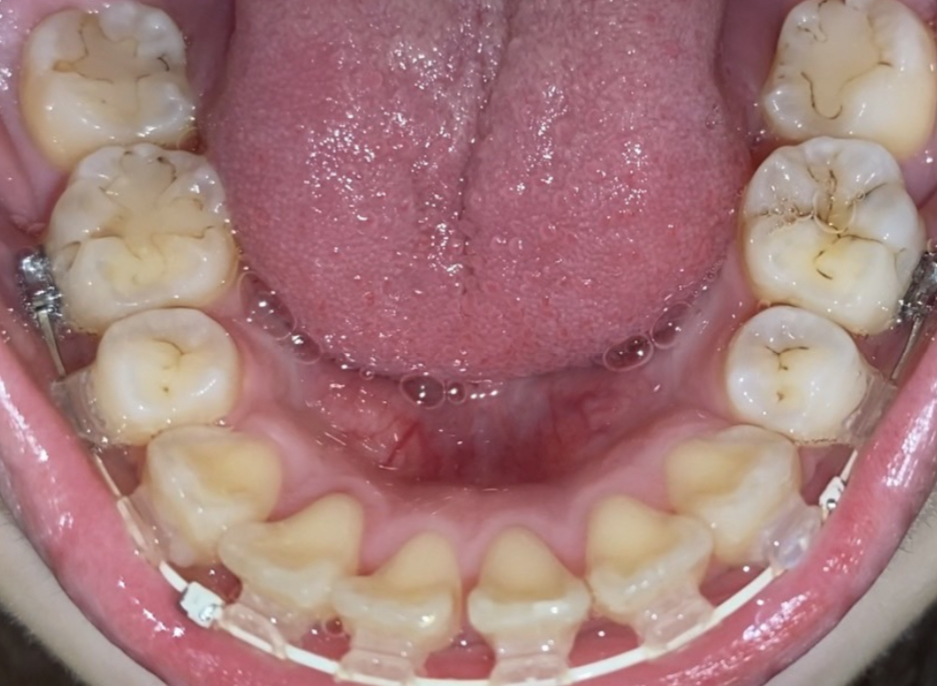

矯正治療中ですが、詰め物の周りが黒くなっているのが気になります。